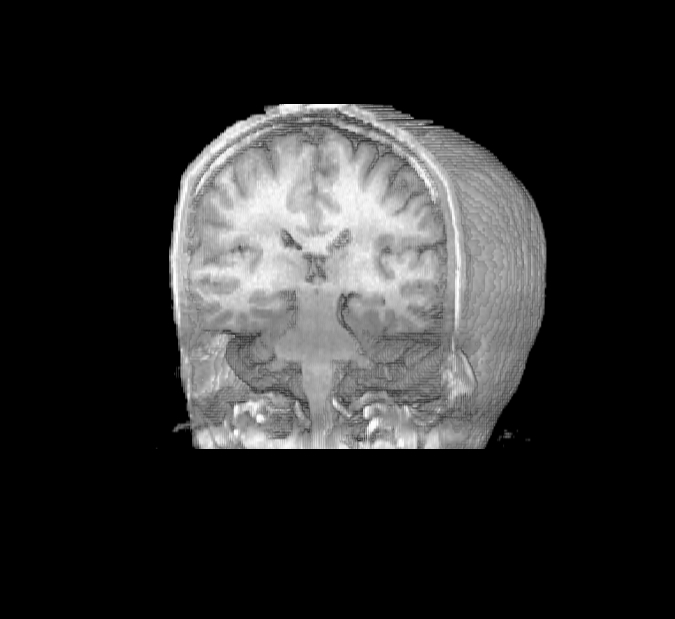

Magnetic resonance imaging (MRI)

Note:

MRI

- Uses rotating magnets to generate image

- Non-invasive

- Can view images from any angle

- Resolution can be less than 1 mm

- Can be adapted to do functional MRI imaging

fMRI

- Oxy-hemoglobin and deoxy-hemoglobin have different magnetic resonance signals

- Brain areas activated by a specific task utilize O2, then a pulse of O2 comes back and creates an influx of oxy-hemoglobin

- Can repeat task many times over

- Spatial resolution– millimeters

- Temporal resolution– seconds

Cerebellum

- Two hemispheres, several lobes divided by fissures

- Neurons in sheets, called cortex

- Receives sensory input from spinal cord, motor info from cerebral cortex, balance info from inner ear and vestibular organs

- Primarily used for motor control, particularly in making postural adjustments and in fine-tuning movements

- Essential for the coordination, planning of movements, learning motor tasks and storing this information

Note:

Cerebellum is latin for 'little brain.'

The cerebellum is located dorsal to the brainstem.

It has two…

Neurons form cortical sheets like in the cerebral hemispheres.

Receives…

fyi: The MRI image is J. Ackman's brain from 2009!